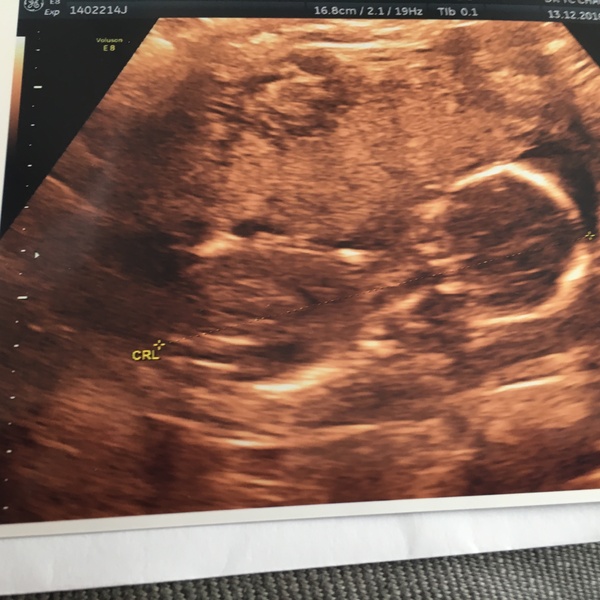

lullaby23 · 13/12/2016 03:32

Had my check up with Dr today all seems fine, heard the heartbeat and quick scan. She's measuring a bit behind for length and a bit ahead for head and tummy - must be taking after me Grin

So cute lullaby!! And great to have a heartbeat fatty, and know everything is ok. We've been on holiday for a week; the distraction of grandparents meant ds really cut his feeds down which was great but now we're home and post holiday blues has set in and he wants milk every 5 minutes, it's driving me nuts!

What a cute picture lullaby glad everything is ok.

Thanks all, so nice to see the little wiggler!